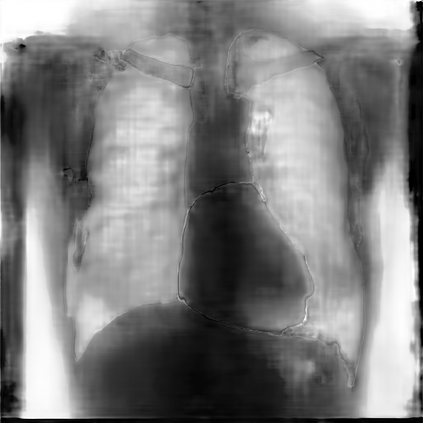

Multi-organ segmentation of X-ray images is of fundamental importance for computer aided diagnosis systems. However, the most advanced semantic segmentation methods rely on deep learning and require a huge amount of labeled images, which are rarely available due to both the high cost of human resources and the time required for labeling. In this paper, we present a novel multi-stage generation algorithm based on Generative Adversarial Networks (GANs) that can produce synthetic images along with their semantic labels and can be used for data augmentation. The main feature of the method is that, unlike other approaches, generation occurs in several stages, which simplifies the procedure and allows it to be used on very small datasets. The method has been evaluated on the segmentation of chest radiographic images, showing promising results. The multistage approach achieves state-of-the-art and, when very few images are used to train the GANs, outperforms the corresponding single-stage approach.